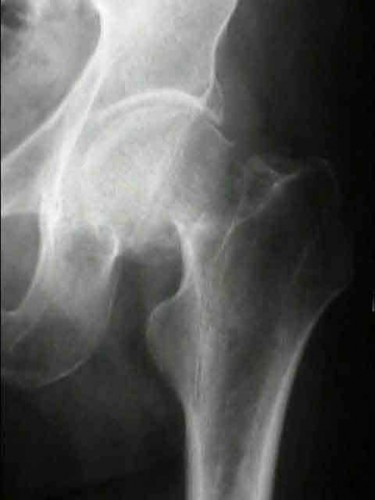

Question 11:

A poly-trauma patient presents hemodynamically unstable with an anteroposterior compression (APC-III) pelvic ring injury. A circumferential pelvic binder is requested to reduce pelvic volume and control hemorrhage. To be anatomically effective, the binder must be centered precisely over which of the following landmarks?

Correct Answer: Greater trochanters

Explanation:

For optimal mechanical advantage and effective reduction of an 'open book' pelvic fracture (APC type), a pelvic binder must be applied directly over the greater trochanters of the femurs. Applying it higher, such as over the iliac crests, is a common error that fails to adequately close the pelvic ring and can paradoxically open the true pelvis.